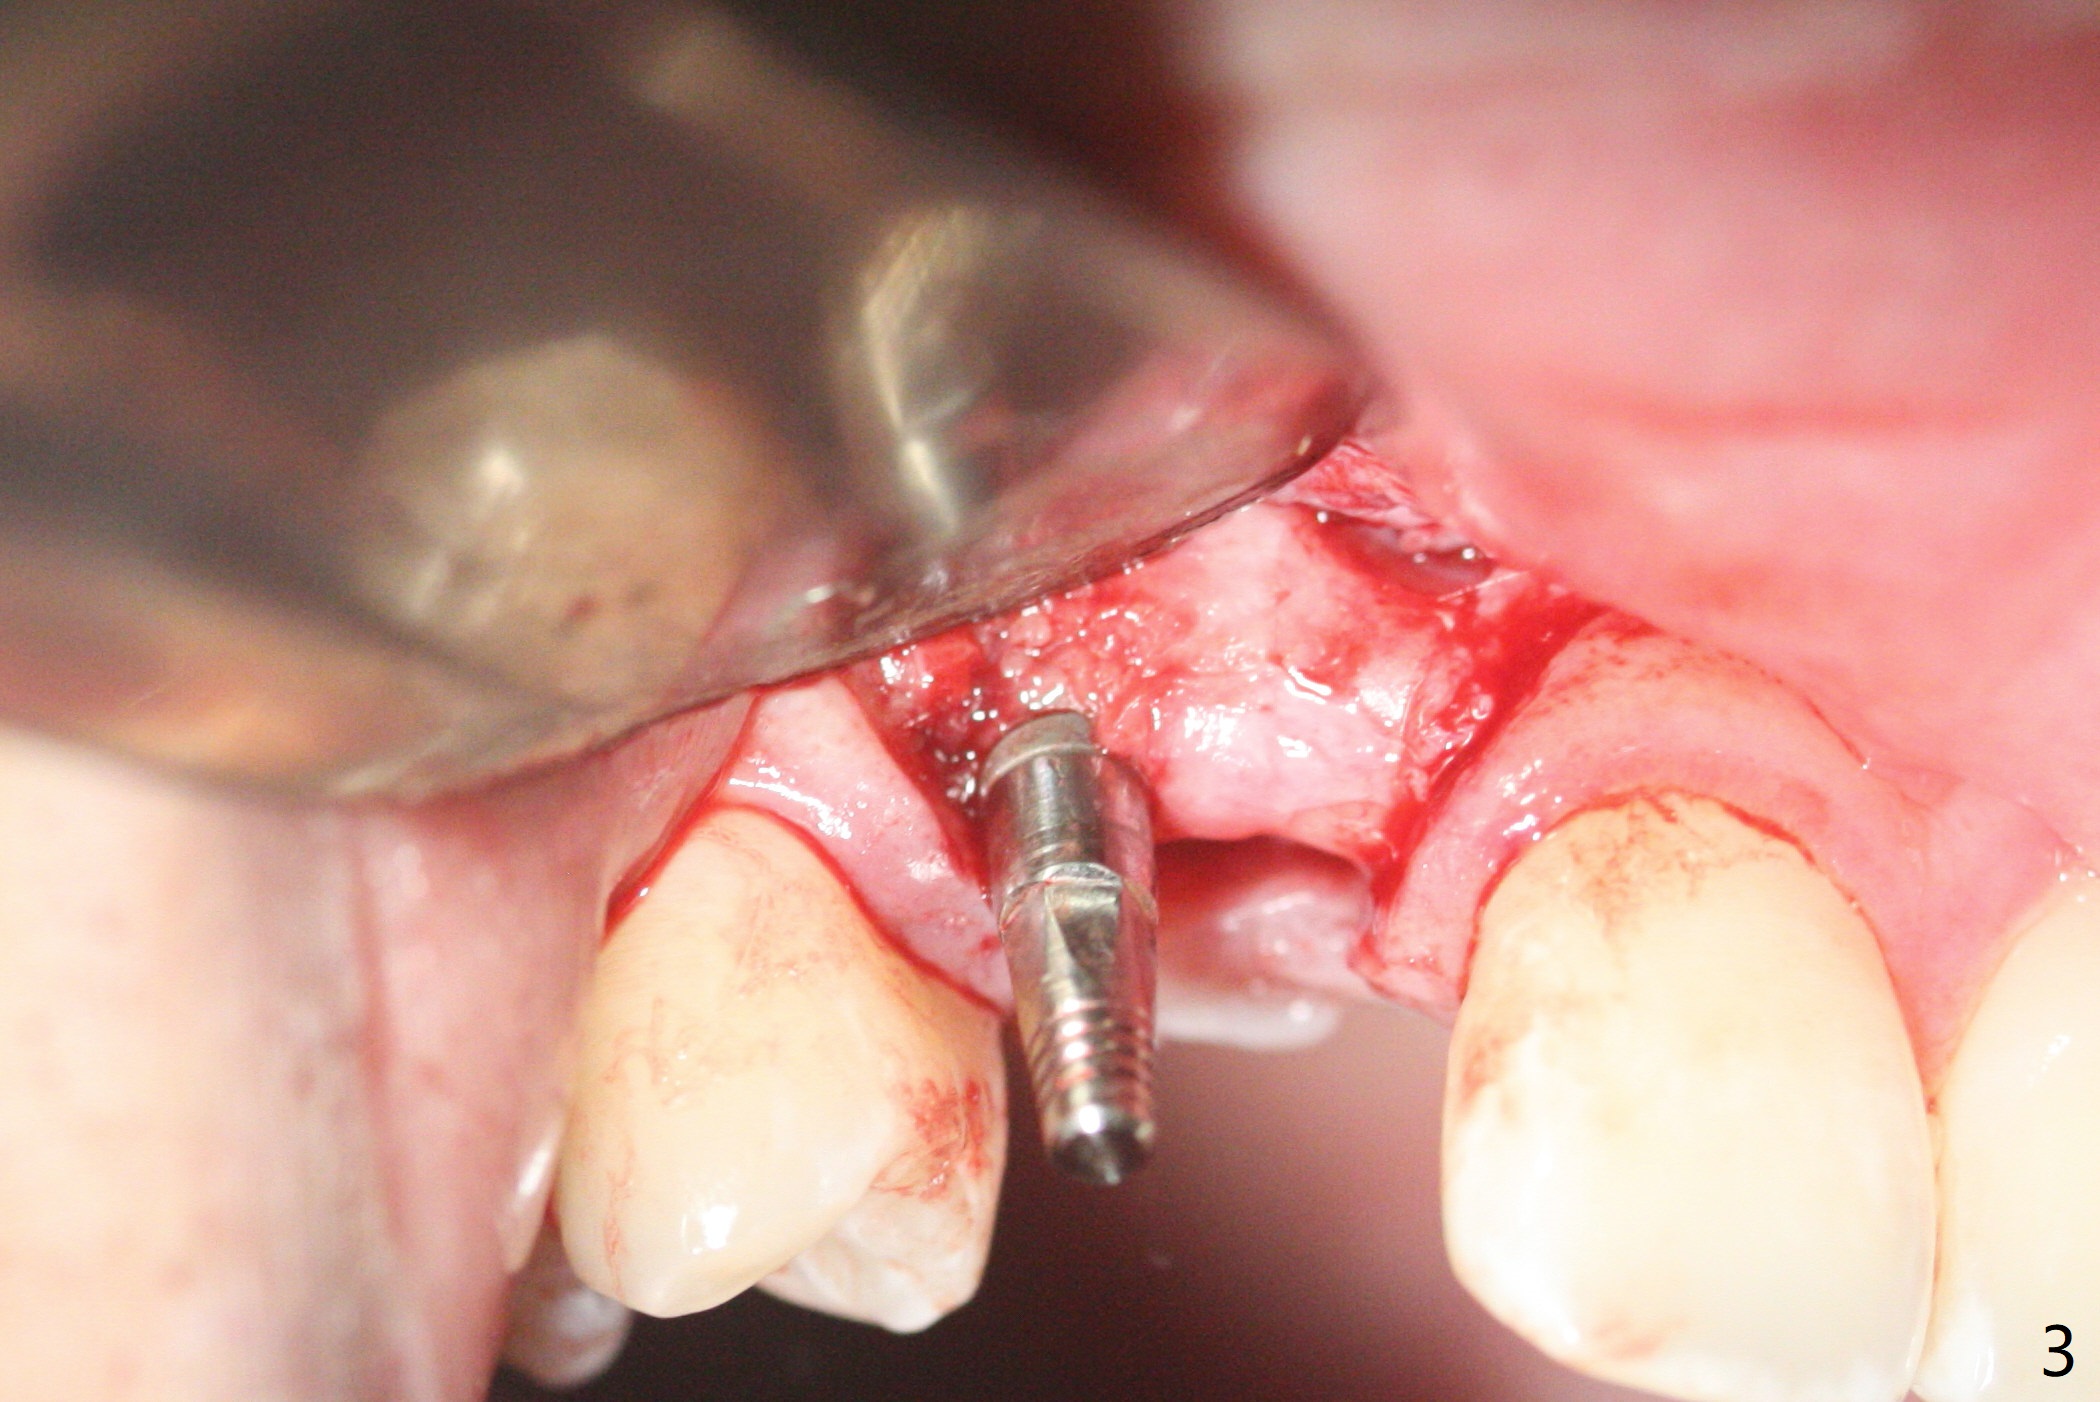

右上尖牙植体拔除,植骨后6个月,切开显示不可吸收膜覆盖的牙槽骨尚饱满(图一),不可吸收膜下面形成一个膜(可能是骨膜,图二:M),在导板指导下,植入3x12(2)毫米一段式植体,颊侧(图三),腭侧(图四)骨下,稍微穿过窦底(图五),植体覆盖粘性骨粉(图六)和PRF膜后,4-0 PGA缝合。伤口有一定张力,使用牙周敷料。术后10天没有疼痛(就没有骨坏死),由于基台存在,牙周敷料没有脱落迹象(图七),也没有撤除。敷料术后13天脱落,伤口好像正常愈合(图八)。由于病人即将回外州上学,提前取模。他喜欢左边牙冠修复形式(牙冠覆盖牙龈),而我们想让牙冠位于牙龈舌侧(图十:T(临时牙冠))。